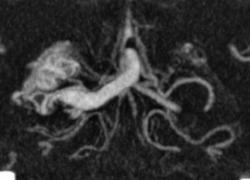

Я чуть увеличил фрагменты изображений с "патологическим состоянием"

Очень наглядна видна сосудистая мальформация.

Питание идет из гипертрофированных задней мозговой и средней мозговой артерий (красные стрелки), дренирование в основном в верхний сагиттальный синус (синий кружок). Дренирующая вена - синие стрелки.